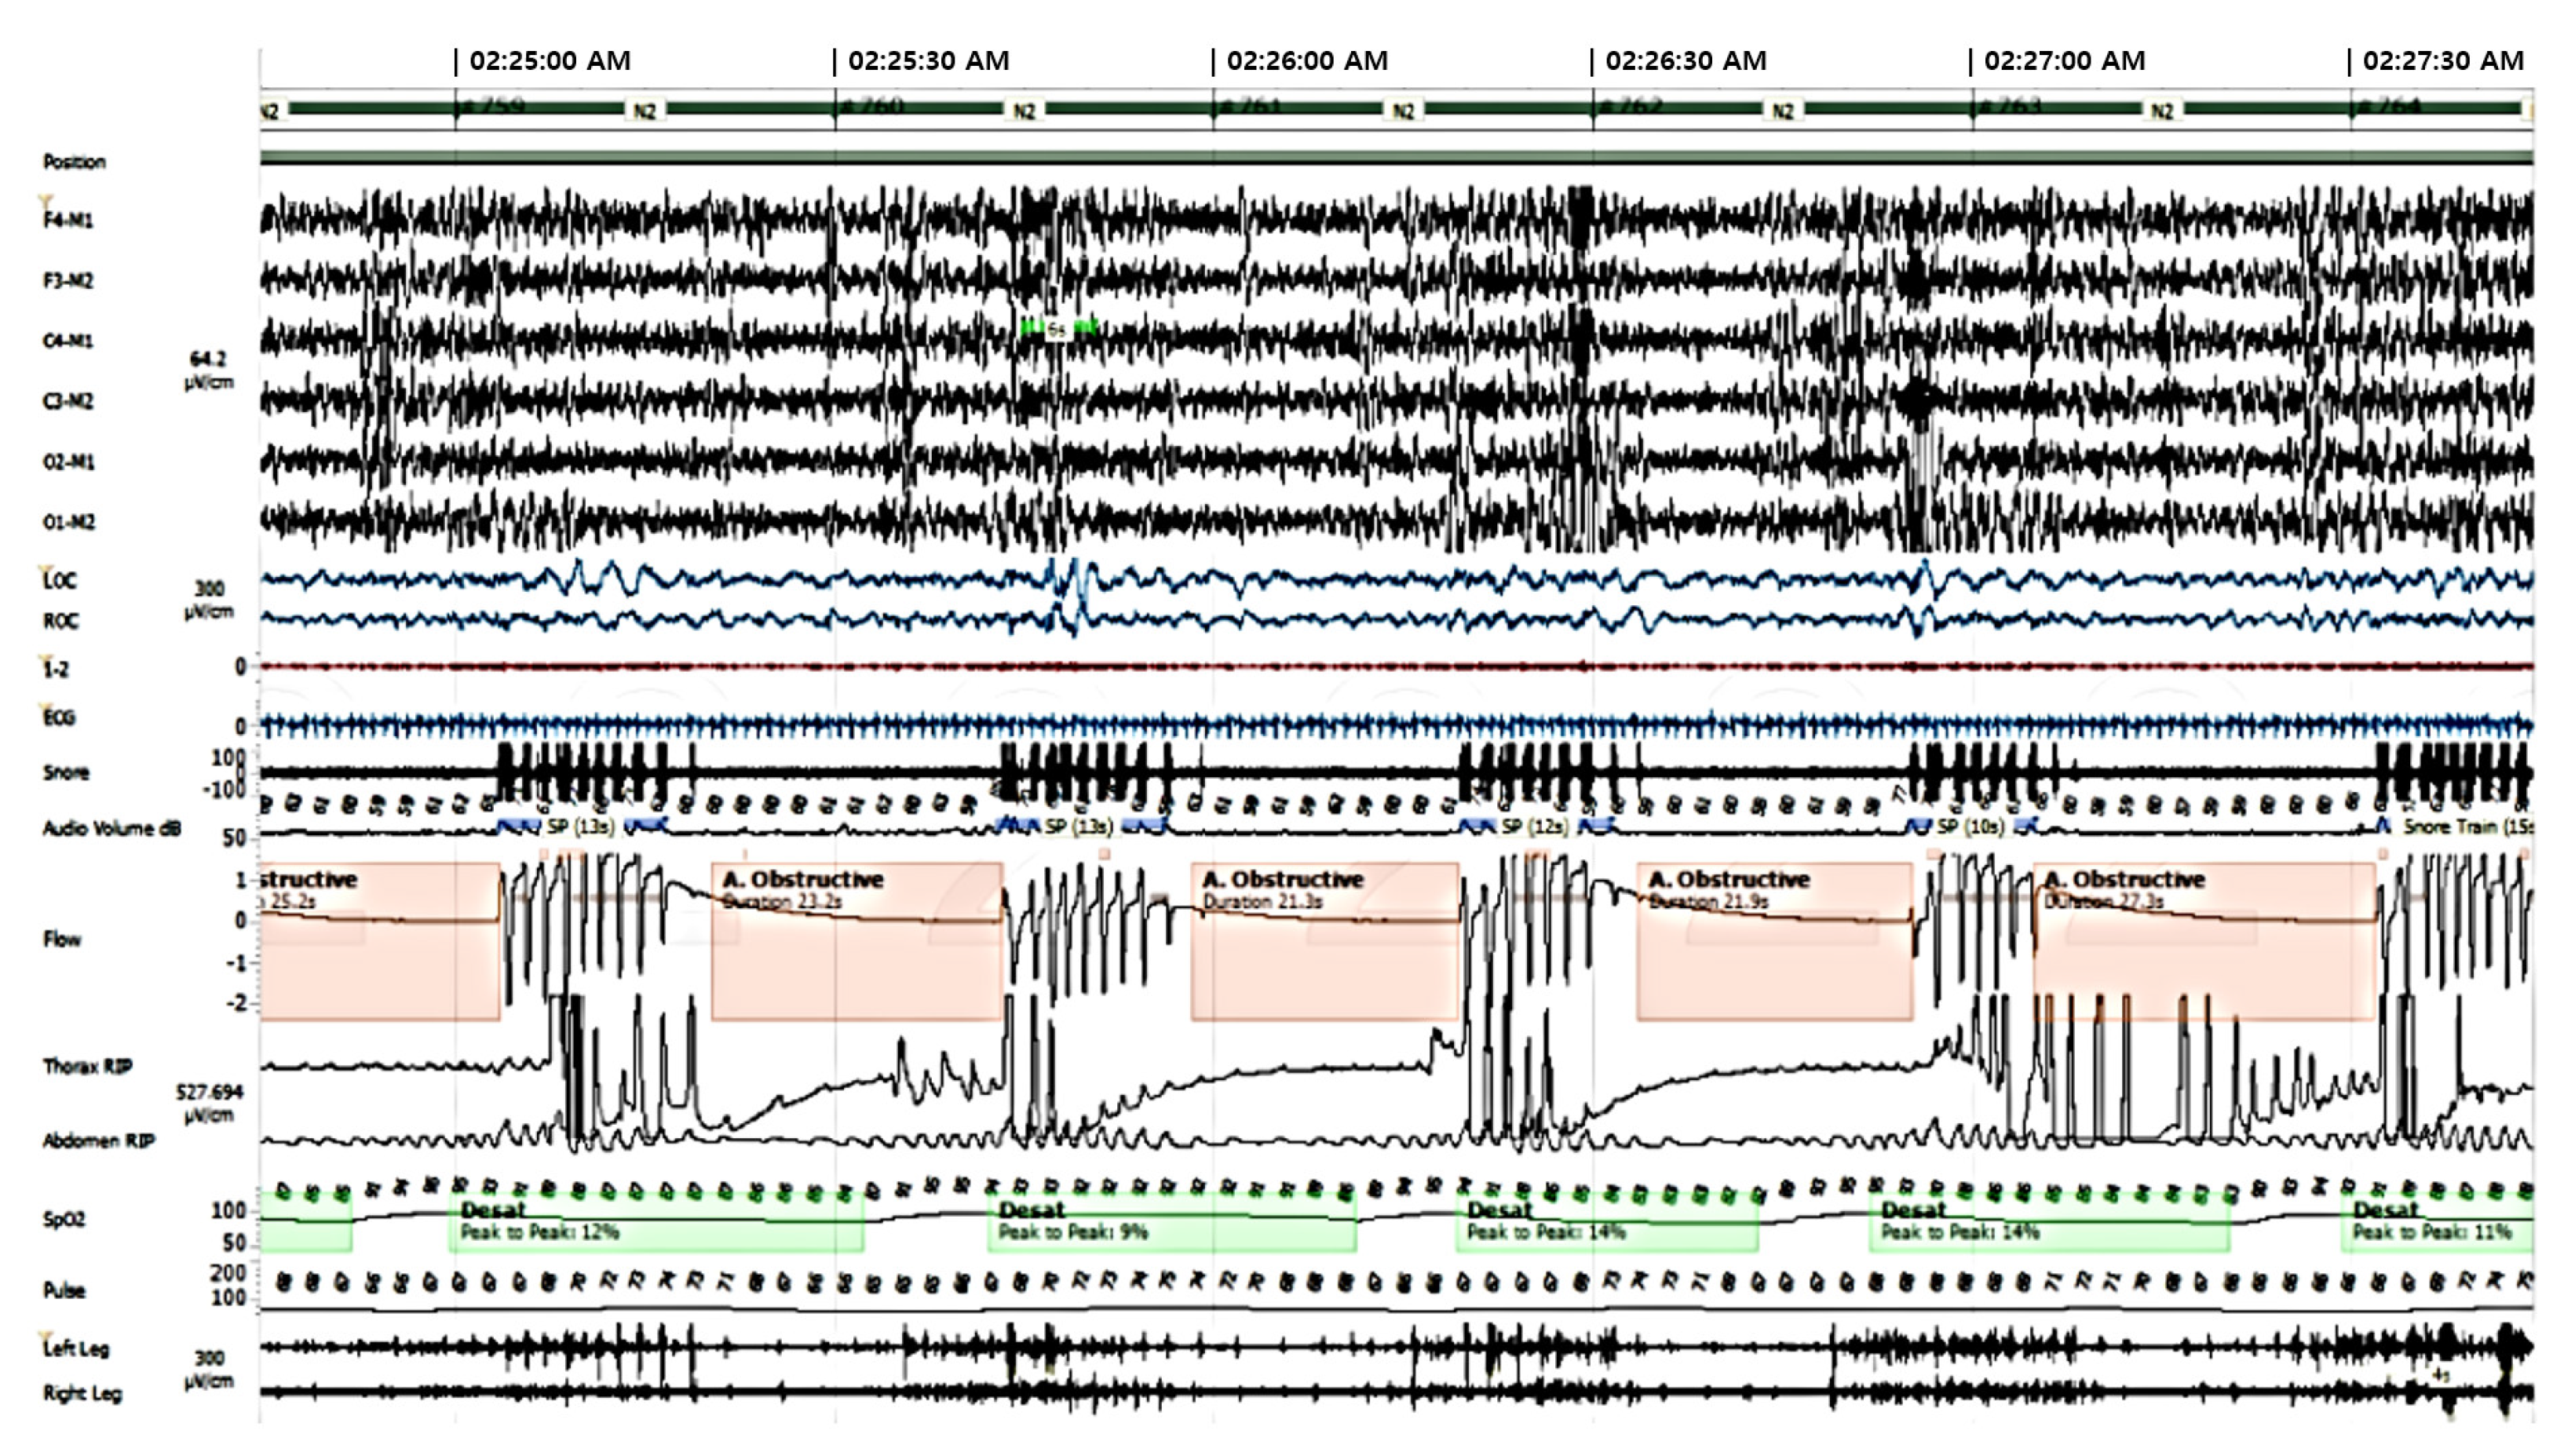

Polysomnogram results indicated severe OSA syndrome with an apnea hypopnea index (AHI) of 88/hour, respiratory disturbance index (RDI) of 88/hour, and nadir oxygen saturation of 74% (Figure 4).

Figure 4. Obstructive sleep apnea on polysomnogram.